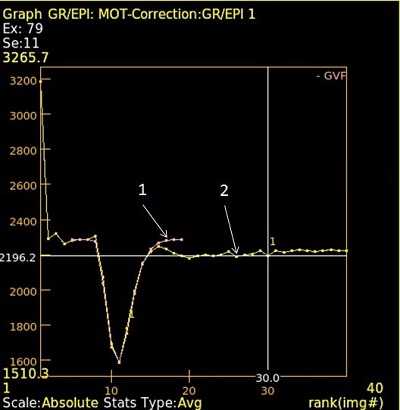

Gamma variate fitting

BrainStat using gamma variate fitting eliminates tracer re-circulation effects.